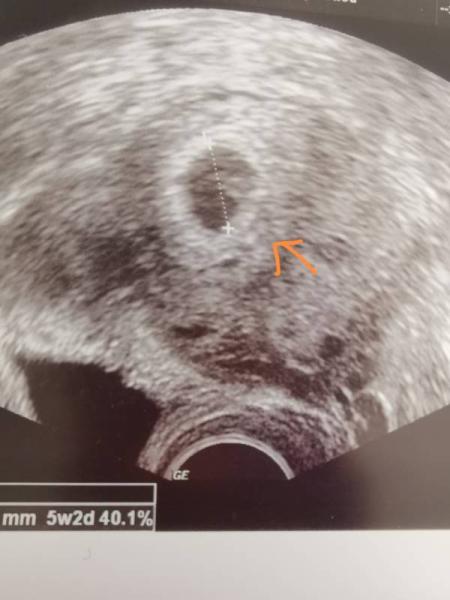

Hallo, Vielleicht kann mich jemand etwas beruhigen . Hatte am 10.04 überraschend positiv getestet, da ich eigentlich die Pille nehme . Wäre also bei 5+4. Habe seit vorgestern leichte Blutungen. Ich war gestern beim FA. Fruchthöhle und Dottersack zu sehen. Wir konnten bei genauem hinsehen auch leicht ein Herzchen schlagen sehen . FA meinte dann neben der Fruchthöhle wäre ein kleines Hämatom (siehe Bild). Soll alles etwas ruhiger angehen, nicht schwer heben, Magnesium nehmen. Progesteron hab ich abgelehnt, da in der letzten Schwangerschaft bei der Blutung in der 9 SSW. die Blutung mehr wurde an statt weniger (Ursache da war unklar). Was mach gerade wahnsinnig macht, ist dass das Blut mal da ist und mal nicht, also ich habe die Blutung nicht durchgängig. Das macht mich wahnsinnig. Man ich bin 41 Jahre alt und habe einen gesunden Sohn und höre mich gerade an wie eine unreife Frau . Aber bin so verunsichert. Liebe Grüße Katrin

Bild zu Frühschwangerschaft und Hämatom - Forum für September - Mamis